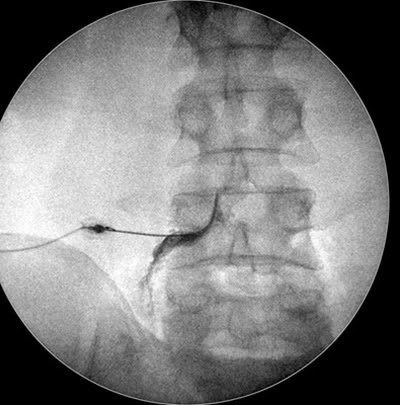

Na infiltração, o neurocirurgião especialista em coluna utiliza equipamentos de imagem para guiar a inserção da agulha em áreas específicas da coluna vertebral.

Bloqueio foraminal na coluna vertebral

Este procedimento é realizado sob efeito de sedação. Ou seja, o paciente adormece e não se lembra de nada, mas mantém a capacidade de respirar normalmente, sem a necessidade de ser entubado. O procedimento de sedação da infiltração, que é conduzido por um médico anestesista, é semelhante ao de uma endoscopia.